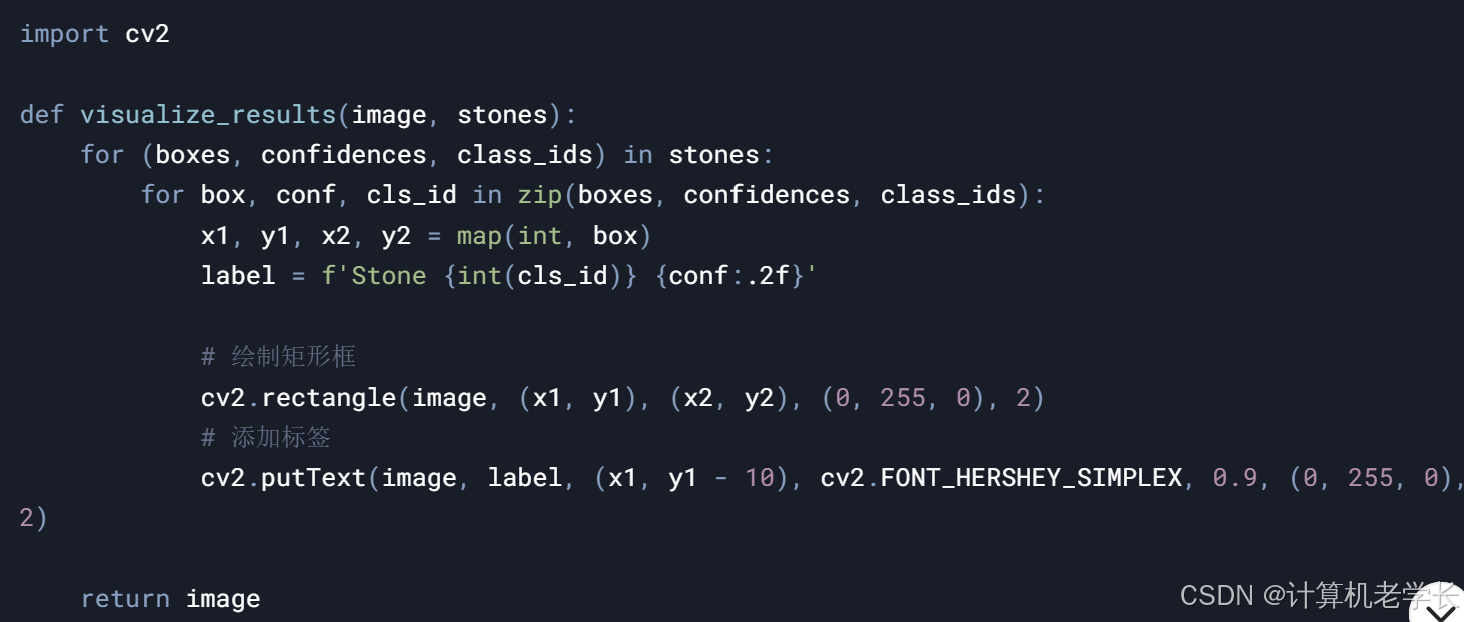

3.2.7 结果可视化模块

结石区域标注

矩形框标注

关键点标注

检测结果展示

检测报告

可视化图像

4.4 结果可视化